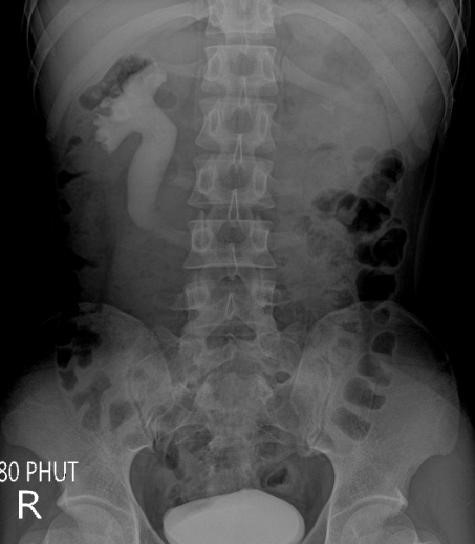

Siêu âm phát hiện thận phải ứ nước độ II, niệu quản trên bên phải dãn, không phát hiện sỏi. Xquang bụng không chuẩn bị không thấy sỏi cản quang đường tiết niệu. Xét nghiệm nước tiểu 10 thông số không thấy hồng cầu và bạch cầu trong nước tiểu. Bệnh nhân được chỉ định chụp niệu đồ tĩnh mạch (UIV). Trên phim UIV thấy thận P ứ nước, niệu quản P đoạn trên dãn có hình chữ "J" ngược, hình ảnh tắc nghẽn niệu quản ngang đốt sống L3, niệu quản bên dưới không thấy (Hình 2).

tietnieu2

Hình 2. UIV cho thấy niệu quản phải dãn có hình chữ "J" ngược, tắc nghẽn ngang L3